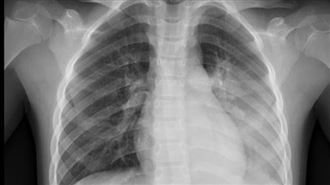

▲大S因流感併發肺炎逝世,享年48歲。(圖/翻攝自IG)

女星大S(徐熙媛)昨遭爆因流感併發肺炎逝世,享年48歲。小S今(3)日透過經紀人證實大S死訊;沒多久,大S的前婆婆張蘭也在在微博上發文,但卻遭中國網友痛批,根本是在蹭熱度,砲轟「你心真壞」。

如今,小S透過經紀人證實死訊,表示「謝謝大家的關心!新年期間,我們全家來日本旅遊,我最親愛善良的姊姊熙媛,因得了流感併發肺炎,不幸地離開了我們」、「感恩這輩子能成為她的姊妹,彼此照顧、相伴,我會永遠感激她、懷念她!珊~一路好走!永遠愛你 together remember forever。」